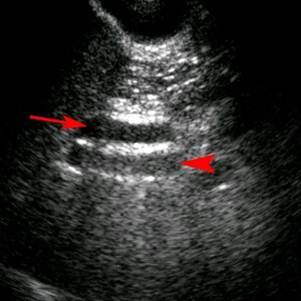

Adenomyomatosis

(Thickened gallbladder wall with comet tail artifact)